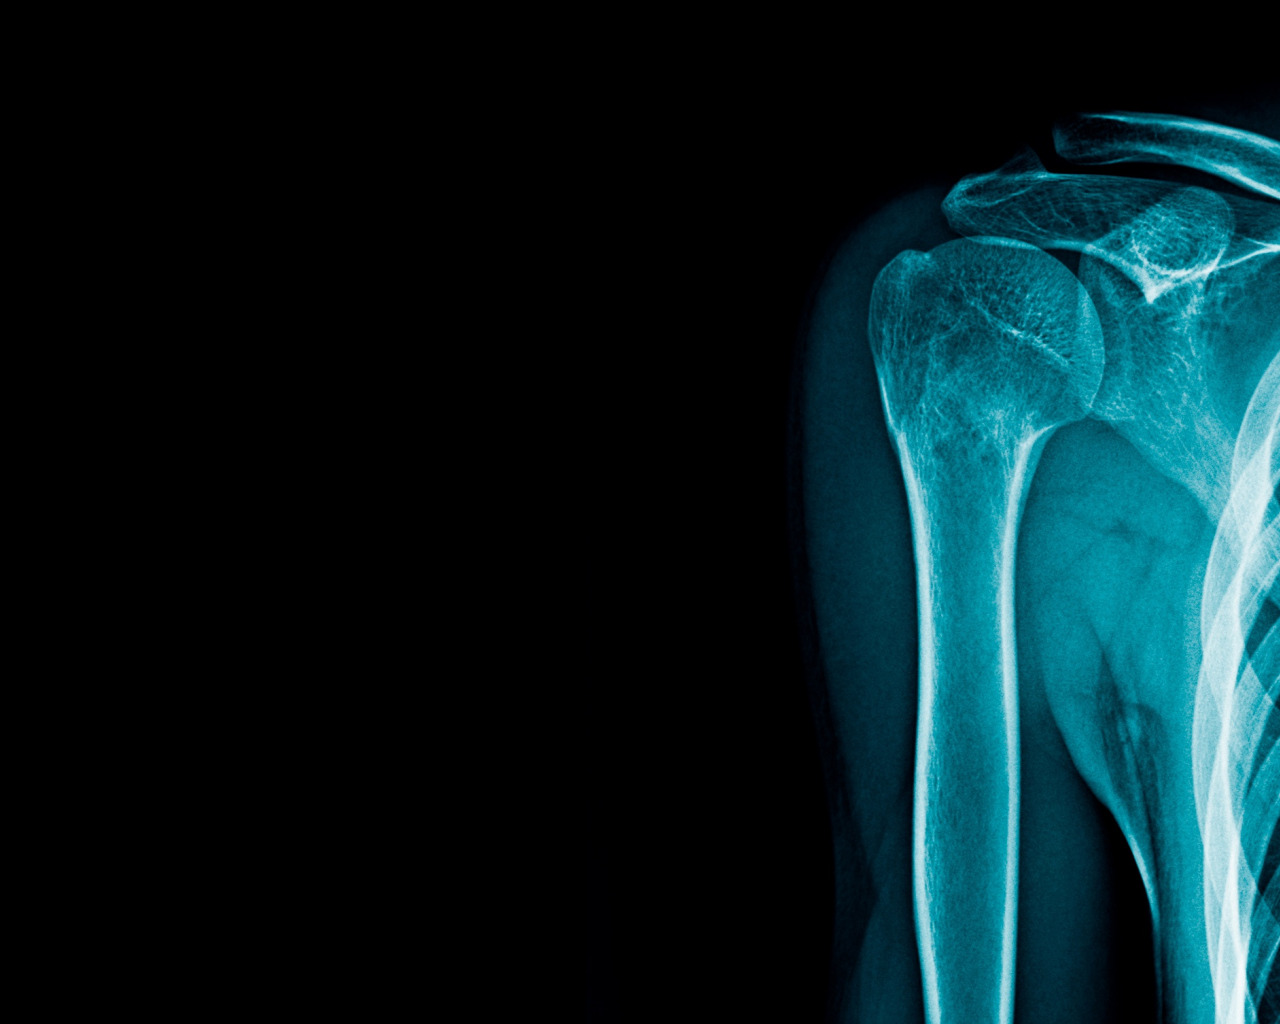

Рентгеновское излучение фото для презентации - 84 фото